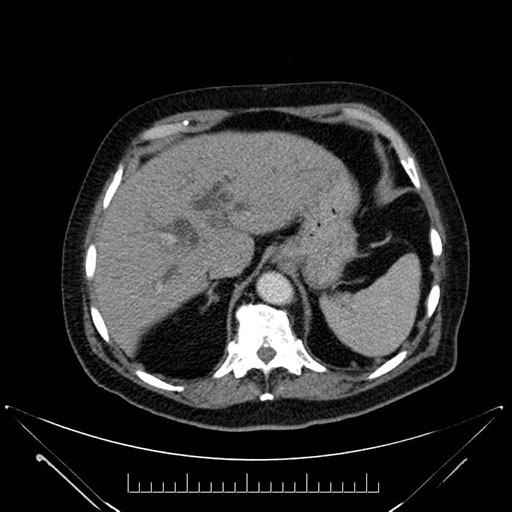

Imaging Analysis

Look through the patient's CT scan to identify any areas of concern for the necessary procedure.

Based on your CT findings, which issue(s) would give reason for "planned slowing down moment(s)" in this case?